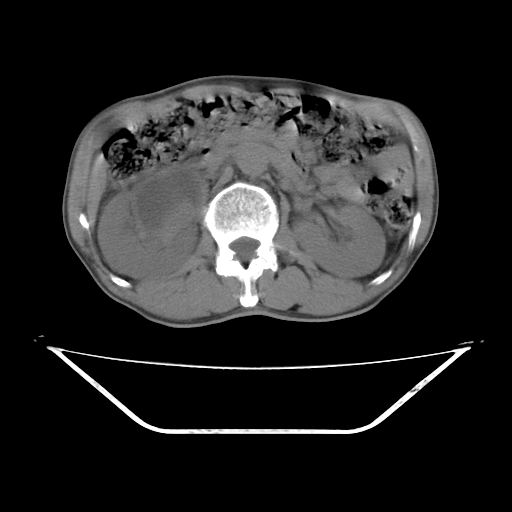

平扫

考虑右肾盂癌,肾动脉受侵,右肾功能减退,右肾盂输尿管积水,管壁增厚,考虑种植转移,应该把下面扫完的

支持右侧肾盂癌伴肾静脉瘤栓形成可能性大,右肾结石.肝右叶后段低密度影,不除外转移.

右肾盂旁ca并肾静脉瘤栓形成/肾功能降低。

右肾结石。

右肾盂癌,肾动脉受侵,右肾盂输尿管积水,管壁增厚,考虑种植转移

支持 右侧肾盂癌伴肾静脉瘤栓形成可能性大,右肾结石;肝右叶后段低密度影,不除外转移。

1.右侧肾盂癌伴肾盂积水。

2.肾脏功能减退,原因有:(1)肾动脉受侵。(2)肾静脉受侵(3)肾积水,等。本例,肾动脉显影较好,但受压明显;肾静脉无明显显示,受压或静脉癌栓,下腔静脉腔内未见明显充盈缺损。

3.右侧上段输尿管扩张,原因:(1)积水所致;(2)种植。